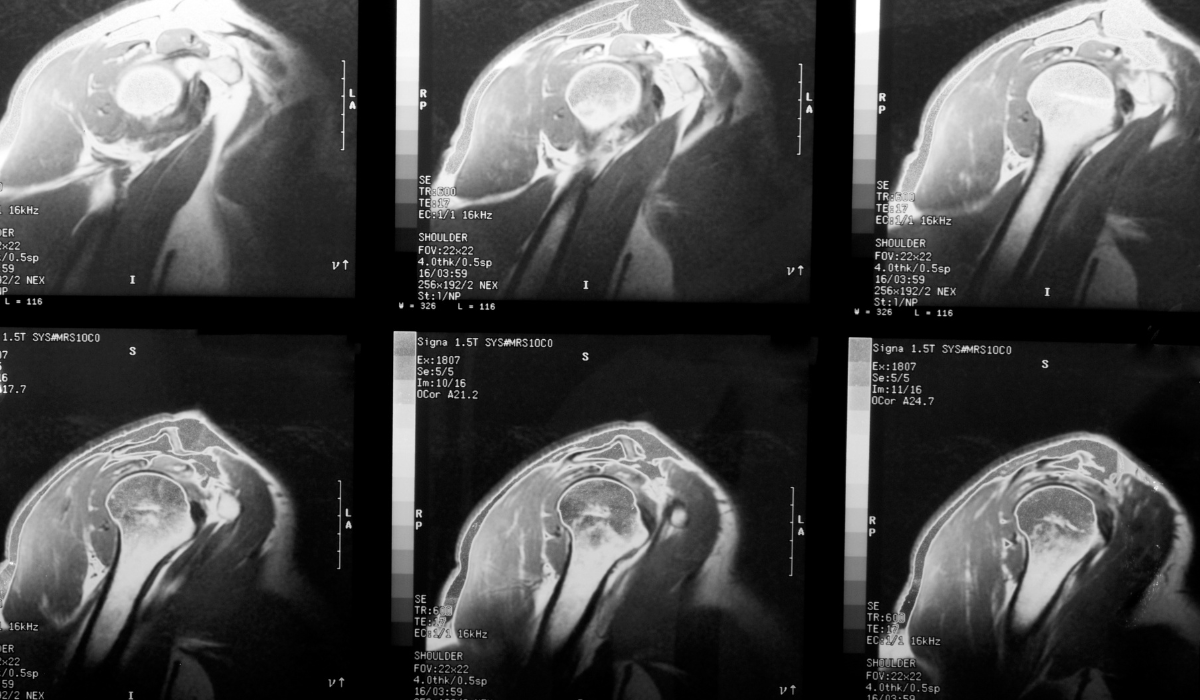

Signs include shoulder pain, especially when lifting the arm, weakness, and difficulty reaching behind your back. An MRI confirms the diagnosis.